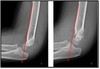

What pathology is present?

Monteggia # | One bone fractured, other bone dislocated